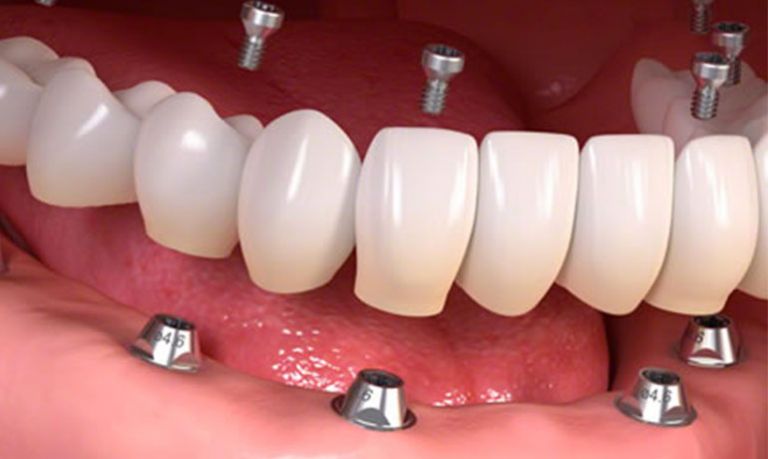

- edentulia totale, ovvero assenza completa dei denti;

Applicazione della protesi definitiva

Una volta completata la guarigione, sull’impianto viene fissata la corona dentale definitiva, progettata per integrarsi armoniosamente con i denti naturali per forma, colore e funzione.

Gli impianti dentali permettono di tornare a masticare in modo efficace e stabile, senza i disagi tipici delle protesi mobili.

Le protesi su impianti sono progettate per imitare fedelmente i denti naturali, contribuendo a un sorriso equilibrato e naturale.